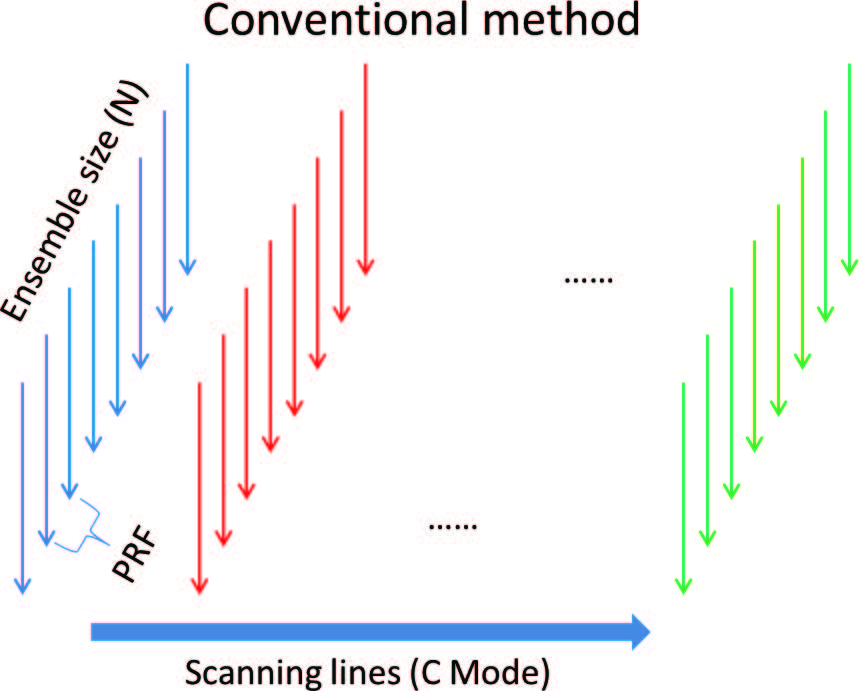

При работе в режиме ЦДК ультразвуковые лучи сканируют отмеченную пользователем область интереса. Для получения цветовой визуализации на экране прибора требуется несколько циклов приема-передачи для обнаружения тока крови и достижения приемлемой точности измерения скорости. Количество подобных циклов зависит от размера сканируемой области и, в среднем, составляет от 8 до 16, а итоговое цветовое изображение является неким компромиссом между точностью измерения скорости и частотой кадров в режиме ЦДК.

При увеличении параметра частоты повторения импульсов (PRF) повышается предел измерения скорости кровотока и увеличивается частота кадров в режиме ЦДК. Однако предел увеличения PRF имеет существенное ограничение по глубине сканирования, поскольку эхосигнал должен проникнуть на глубину исследуемой области, отразиться и вернуться назад в пределах одного цикла. Например, при исследовании на сонной артерии, расположенной на глубине от 4 до 5 см. максимальное значение PRF составляет примерно 15 кГц (формула расчета PRF = 1/ (глубина_сканирования х 2 / С), где С – средняя скорость ультразвука в биологических тканях (1540 м/с)). Если размер регистрируемой области принять равным 10, то частота кадров будет равна примерно 15 Гц для изображения, состоящего из 100 линий. Описанный процесс также проиллюстрирован на рисунке 1. Дальнейшее увеличение параметра PRF приведет к критически низкому временному разрешению сканирования, что недопустимо для исследования на артериях с высокой скоростью кровотока. Что, в свою очередь, значительно затрудняет диагностику в случае стеноза сонной артерии.

Другим недостатком классического режима ЦДК является то, что временной интервал каждой итерации формирования строки изображения критически велик и, поскольку изображение формируется последовательно строка за строкой, то каждая сформированная строка изображения фактически обозначает скорость в разный момент времени.